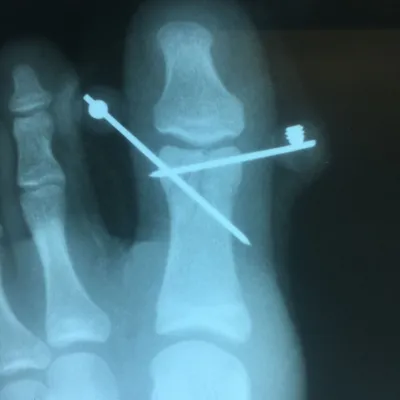

Pre and Postop ORIF Displaced Big Toe Intra-articular Pediatric Fracture (Below)

This is post-operative x-ray of a repair of a fracture of the long bone of foot connected to the great toe, There are three pins holding the fracture fragments in place, and once this heals the pins are removed.